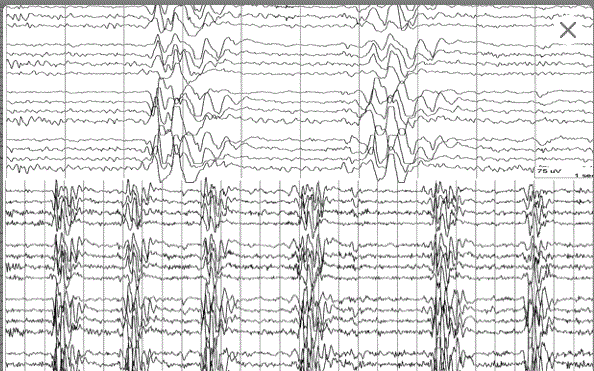

Diagnosis?

Hypsarrhythmia

note disorganized background with multi focal spikes